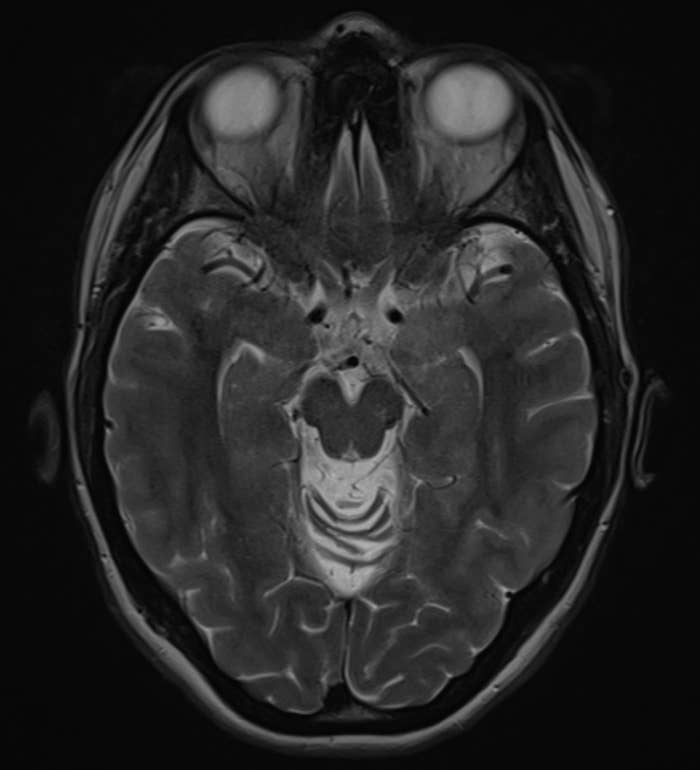

Dementia affects aggregate encephalon functions, including memory, circadian rhythm, and behavior. “So aboriginal illness tin disrupt the assemblage timepiece and mean slumber architecture,” said board-certified neurologist Dr. Rob Nawaz Khan. What precisely does this look like? Ahead, experts interruption down the slumber problems that could beryllium signs of dementia.